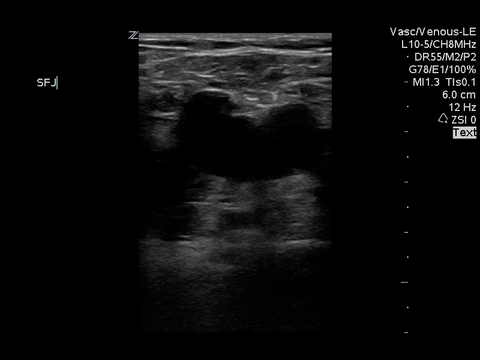

Right lower extremity

In each of these images it appears the vein fully collapses with compression. We can conclude that there is likely no DVT present within the limitations of the 2-point compression scan (see discussion for further details)